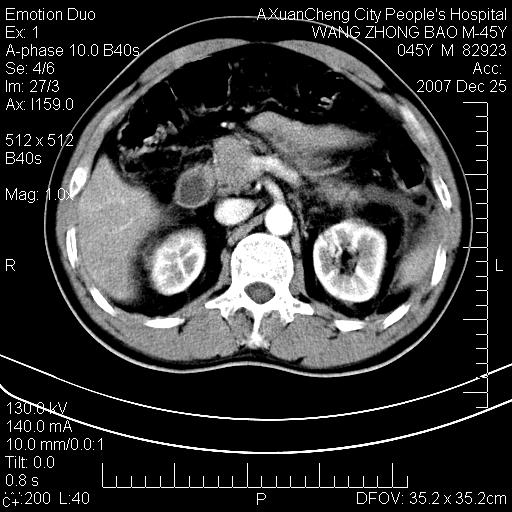

以下是引用qiuleiyu在2007-12-25 18:14:00的发言:[br]胰腺增大,周边渗出改变,肾前筋膜明显增厚,示少量积液.胆囊壁毛糙,周边少许渗出,胆总管壁厚,异常强化,然扩张不明显.结合病程急短;考虑;胆管炎,胆囊炎,胆源性胰腺炎可能大,请结合实验室检查及随访.

以下是引用lisihao在2007-12-25 14:23:00的发言:[br]急性水肿型胰腺炎[br]依据:1、胰腺弥漫性肿大,边缘稍毛糙;[br] 2、双侧肾周筋膜增厚,尤以左侧为甚(重要征象)[br] 3、双侧后胸膜增厚(刺激性炎症);[br] 4、结合病史,查血尿淀粉酶应该可以确诊。